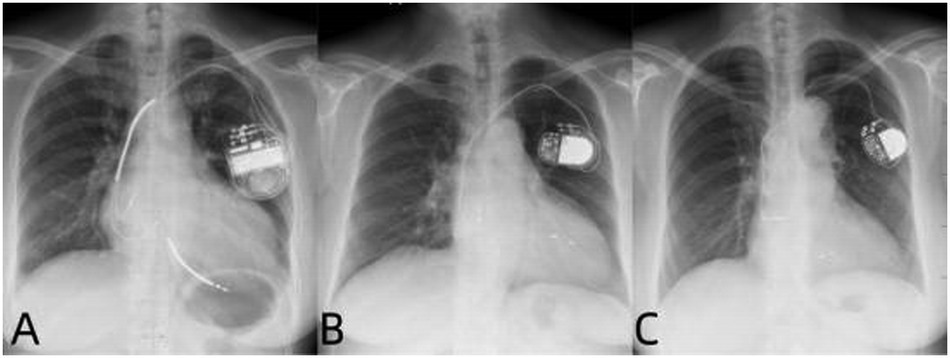

Patients underwent conventional biventricular pacing:Right ventricular lead implanted at the apex;Left ventricular lead placed in the coronary sinus lateral vein (Figure 2).

Figure 2

Postoperative x-ray images of three types of pacemaker mplantations. (A–C) Are the x-ray images after the implantation of BVP, LUVP-SVP, and LUVP-LBBAP respectively.